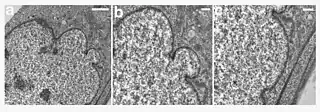

HPGS is caused by mutations that weaken the structure of the cell nucleus, making normal cell division difficult. The histone mark H4K20me3 is involved and caused by de novo mutations that occur in a gene that encodes lamin A. Lamin A is made but is not processed properly. This poor processing creates an abnormal nuclear morphology and disorganized heterochromatin. Patients also do not have appropriate DNA repair, and they also have increased genomic instability.[14]

In HGPS, the recognition site that the enzyme requires for cleavage of prelamin A to lamin A is mutated. Lamin A cannot be produced, and prelamin A builds up on the nuclear membrane, causing a characteristic nuclear blebbing.[32] This results in the symptoms of progeria, although the relationship between the misshapen nucleus and the symptoms is not known.

A study that compared HGPS patient cells with the skin cells from young and elderly normal human subjects found similar defects in the HGPS and elderly cells, including down-regulation of certain nuclear proteins, increased DNA damage, and demethylation of histone, leading to reduced heterochromatin.[33] Nematodes over their lifespan show progressive lamin changes comparable to HGPS in all cells but neurons and gametes.[34] These studies suggest that lamin A defects are associated with normal aging.[33][35]